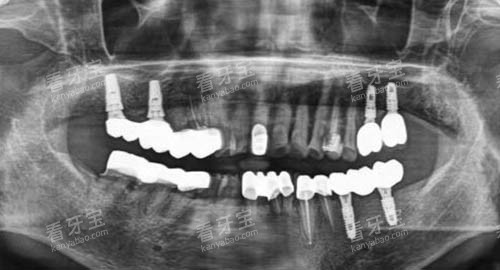

为了给患者提供更加比较准、较高的效率的口腔医疗服务,大连齿医生口腔引进了一系列国内外靠前的口腔医疗设备。

这些设备包括智能化口腔全景机、口腔 CT、激光治疗仪等。

智能化口腔全景机能够快速、更准地拍摄口腔全景图像,为医生提供超全的口腔信息,有助于医生做出更加更准的诊断;口腔 CT 则可以提供三维立体的口腔影像,让医生更加清晰地了解患者口腔内部的结构和病变情况;激光治疗仪在治疗口腔疾病时,具有创伤小、疼痛轻、修养快等优点,能够为患者减轻痛苦。